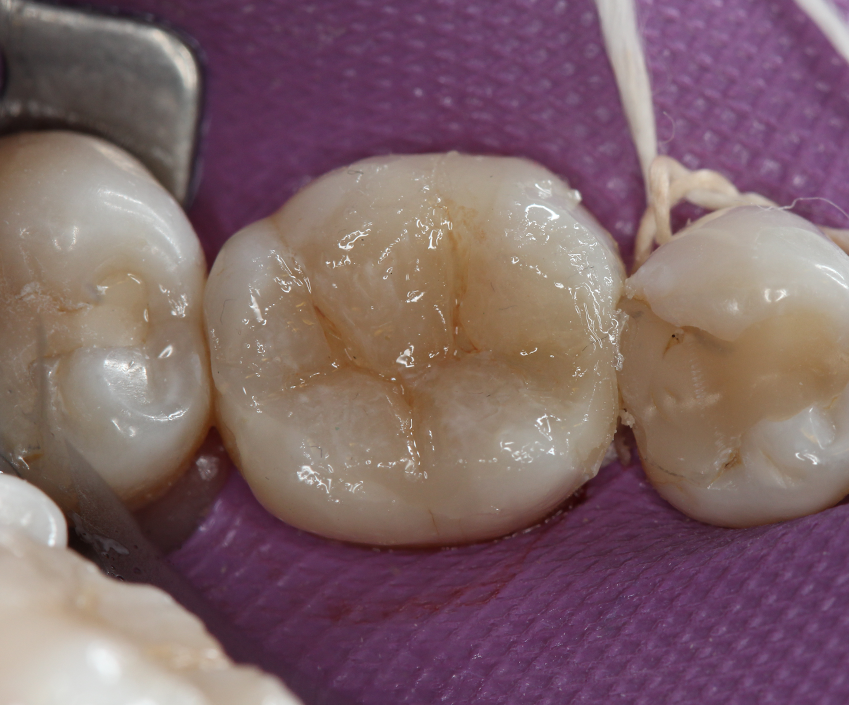

Mesial and buccal boxes of the Class II cavity were closed using the incremental layer technique with a conventional resin composite (IPS Empress Direct, Ivoclar Vivadent), and with the help of a metallic matrix system (Triodent V3 Ring, Dentsply Sirona), transforming it into a Class I cavity (Figs. 7 and 8).

Fig. 7 Fig. 8

The restorative procedure continued by filling the cavity to the occlusal cavosurface margin with a single layer (Fig. 9) of a regular consistency bulk fill composite (Tetric EvoCeram Bulk Fill). Stain was added to enhance the occlusal pits delimitations and optically give depth to the final restoration (Fig. 10), followed by the application of an enamel bonding agent (Heliobond, Ivoclar Vivadent) to serve as a fissure sealant and prevent abrasion and leaching of the pigments. Each step was followed by light-curing (Bluephase 20i), and a final light-curing protocol was performed with glycerin gel in order to polymerize the composite oxygen-inhibition layer. Final aspect of the restoration was evaluated after removal of the rubber dam (Fig. 11).

Fig. 9 Fig. 10